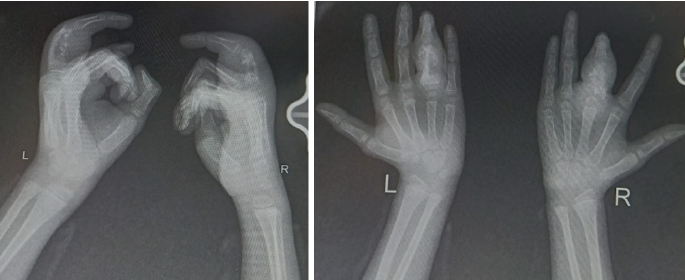

At 3 months, radiographs demonstrated complete good healing with cortical restoration (Fig. 5). The patient achieved a full range of motion without deformity. A structured rehabilitation program, including active and passive exercises and grip strengthening, ensured complete functional recovery.

Figure 5: Follow-up radiographs of the patient on anti-tubercular therapy for 3 months.